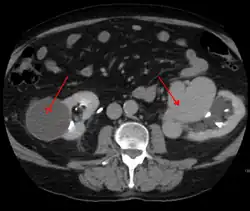

An arterial venous malformation of the left kidney and a simple cyst of the right kidney

An arterial venous malformation of the left kidney leading to aneurysmal dilatation of the left renal vein and inferior vena cava